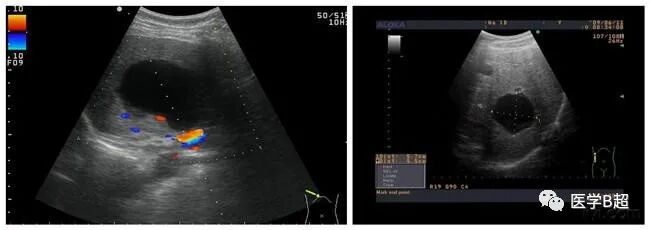

血管瘤、肝囊肿

别把血管瘤、肝囊肿当肝癌。b超md是什么意思肝脏B超报告单常见术语全在这里!_https://www.jmylbn.com_新闻资讯_第3张

现在,B超的应用越来越广泛了,越来越多的无症状的先天性肝囊肿和血管瘤被发现。尤其是肝炎患者,因为经常做B超,发现得也最多。这往往引起患者的恐慌。因为患者知道,肝炎常可引起肝癌,所以对肝脏里看到的一点点占位性病变都非常敏感。

如果是肝囊肿,患者不必害怕,因为囊肿大多是先天性的。“肝血管瘤”并不是恶性肿瘤,它大多数为海绵状血管瘤,是肝脏最常见的良性肿瘤,可发生于任何年龄,很多人在体检的时候都会发现有血管瘤。血管瘤的发展非常缓慢,小血管瘤可无任何症状,大多数是在体检时被B超发现。一般说来小的肝囊肿和血管瘤对人体健康没有多大影响,患者不必紧张,也无需处理,只有较大的肝囊肿和血管瘤才需要外科手术或介入治疗。